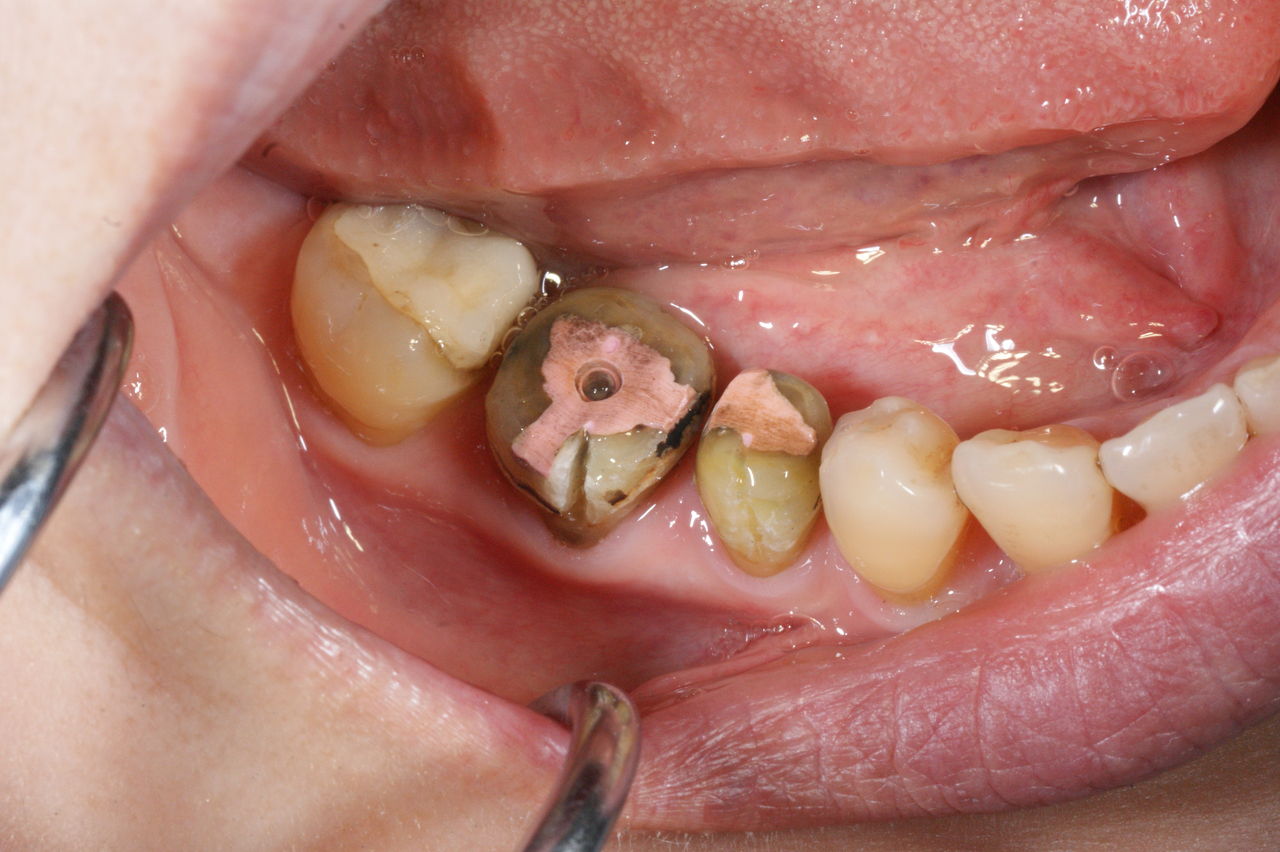

425.審美性 2019年06月21日 14:51 開口時、真っ先に金属歯が眼に入ります。 人工的な装着物が入っているのに、それを感じさせず、未治療の歯と調和して、自然に見えること。それが審美の審美たる所以ではないでしょうか!?(大) 「審美治療」カテゴリの最新記事 「修復治療」カテゴリの最新記事 < 前の記事次の記事 > コメント コメントフォーム 名前 コメント 評価する リセット リセット 顔 星 投稿する 情報を記憶